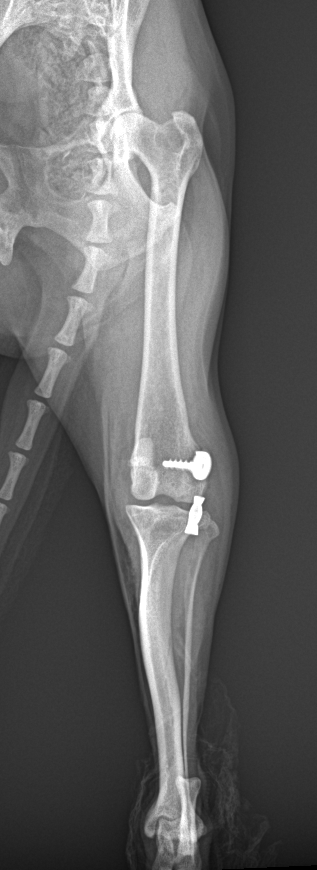

高齢犬の前十字靭帯断裂

慢性疾患を患っている犬が前十字靭帯を痛め、内科的に管理しているが改善する様子が見られないので、なんとかしてほしいと連絡がありました。X線では脛骨の前方変位が著しく、患肢への負重も弱い状態でした。高齢犬のため従来のCBLOなどの骨きり矯正は行わず、ラテラルスーチャー変法で整復しました。大腿骨遠位の種子骨領域にアンカースクリューに人工靭帯をスパイクワッシャーで固定し、脛骨近位に作成した骨孔と締結しました。慢性疾患が表面化する麻酔のリスクもあると考えられましたが、無事に整復が終了しました。特に小型犬であったため、従来からのこの方法はたいへん有効です。